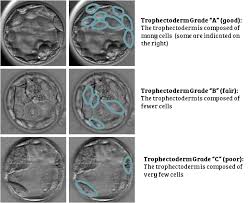

Blastocyst-morphology grading system based on the criteria established by Gardner and Schoolcraft. You may receive a report with a number and 2 letter grades for the two different parts of each blastocyst the inner cell mass or ICM which is what becomes the fetus and the outer layer called the trophectoderm or TE which is what becomes the. Blastocyst development stage inner cell mass quality and trophectoderm quality.

We demonstrate a positive correlation between the calculated BQS score and cell number by staining thawed human embryos and suggest that BQS can be applied to evaluate culture systems clinically. Blastocyst development ranking from 36 ICM quality as A B or C. There are three major components to blastocyst stage embryo grading when using a classification system known as Gardner-Schoolcraft scoring named after the two people who came up with it.